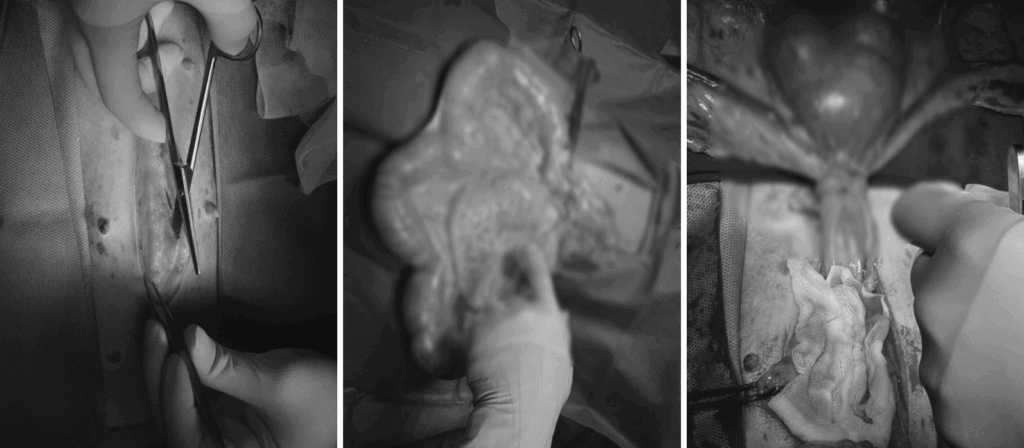

자궁축농증 수술 사진 / 온숲동물의료센터

자궁 내 분비물 / 출처: 온숲동물의료센터

자궁 적출 및 수술 사진 / 출처: 온숲 동물의료센터

수술은 저희 김영웅 대표원장님과 정형운 대표원장님이 직접 집도하셨습니다.

심하게 확장된 자궁은 안전하게 제거되었으며, 수술은 무사히 마무리되었습니다.